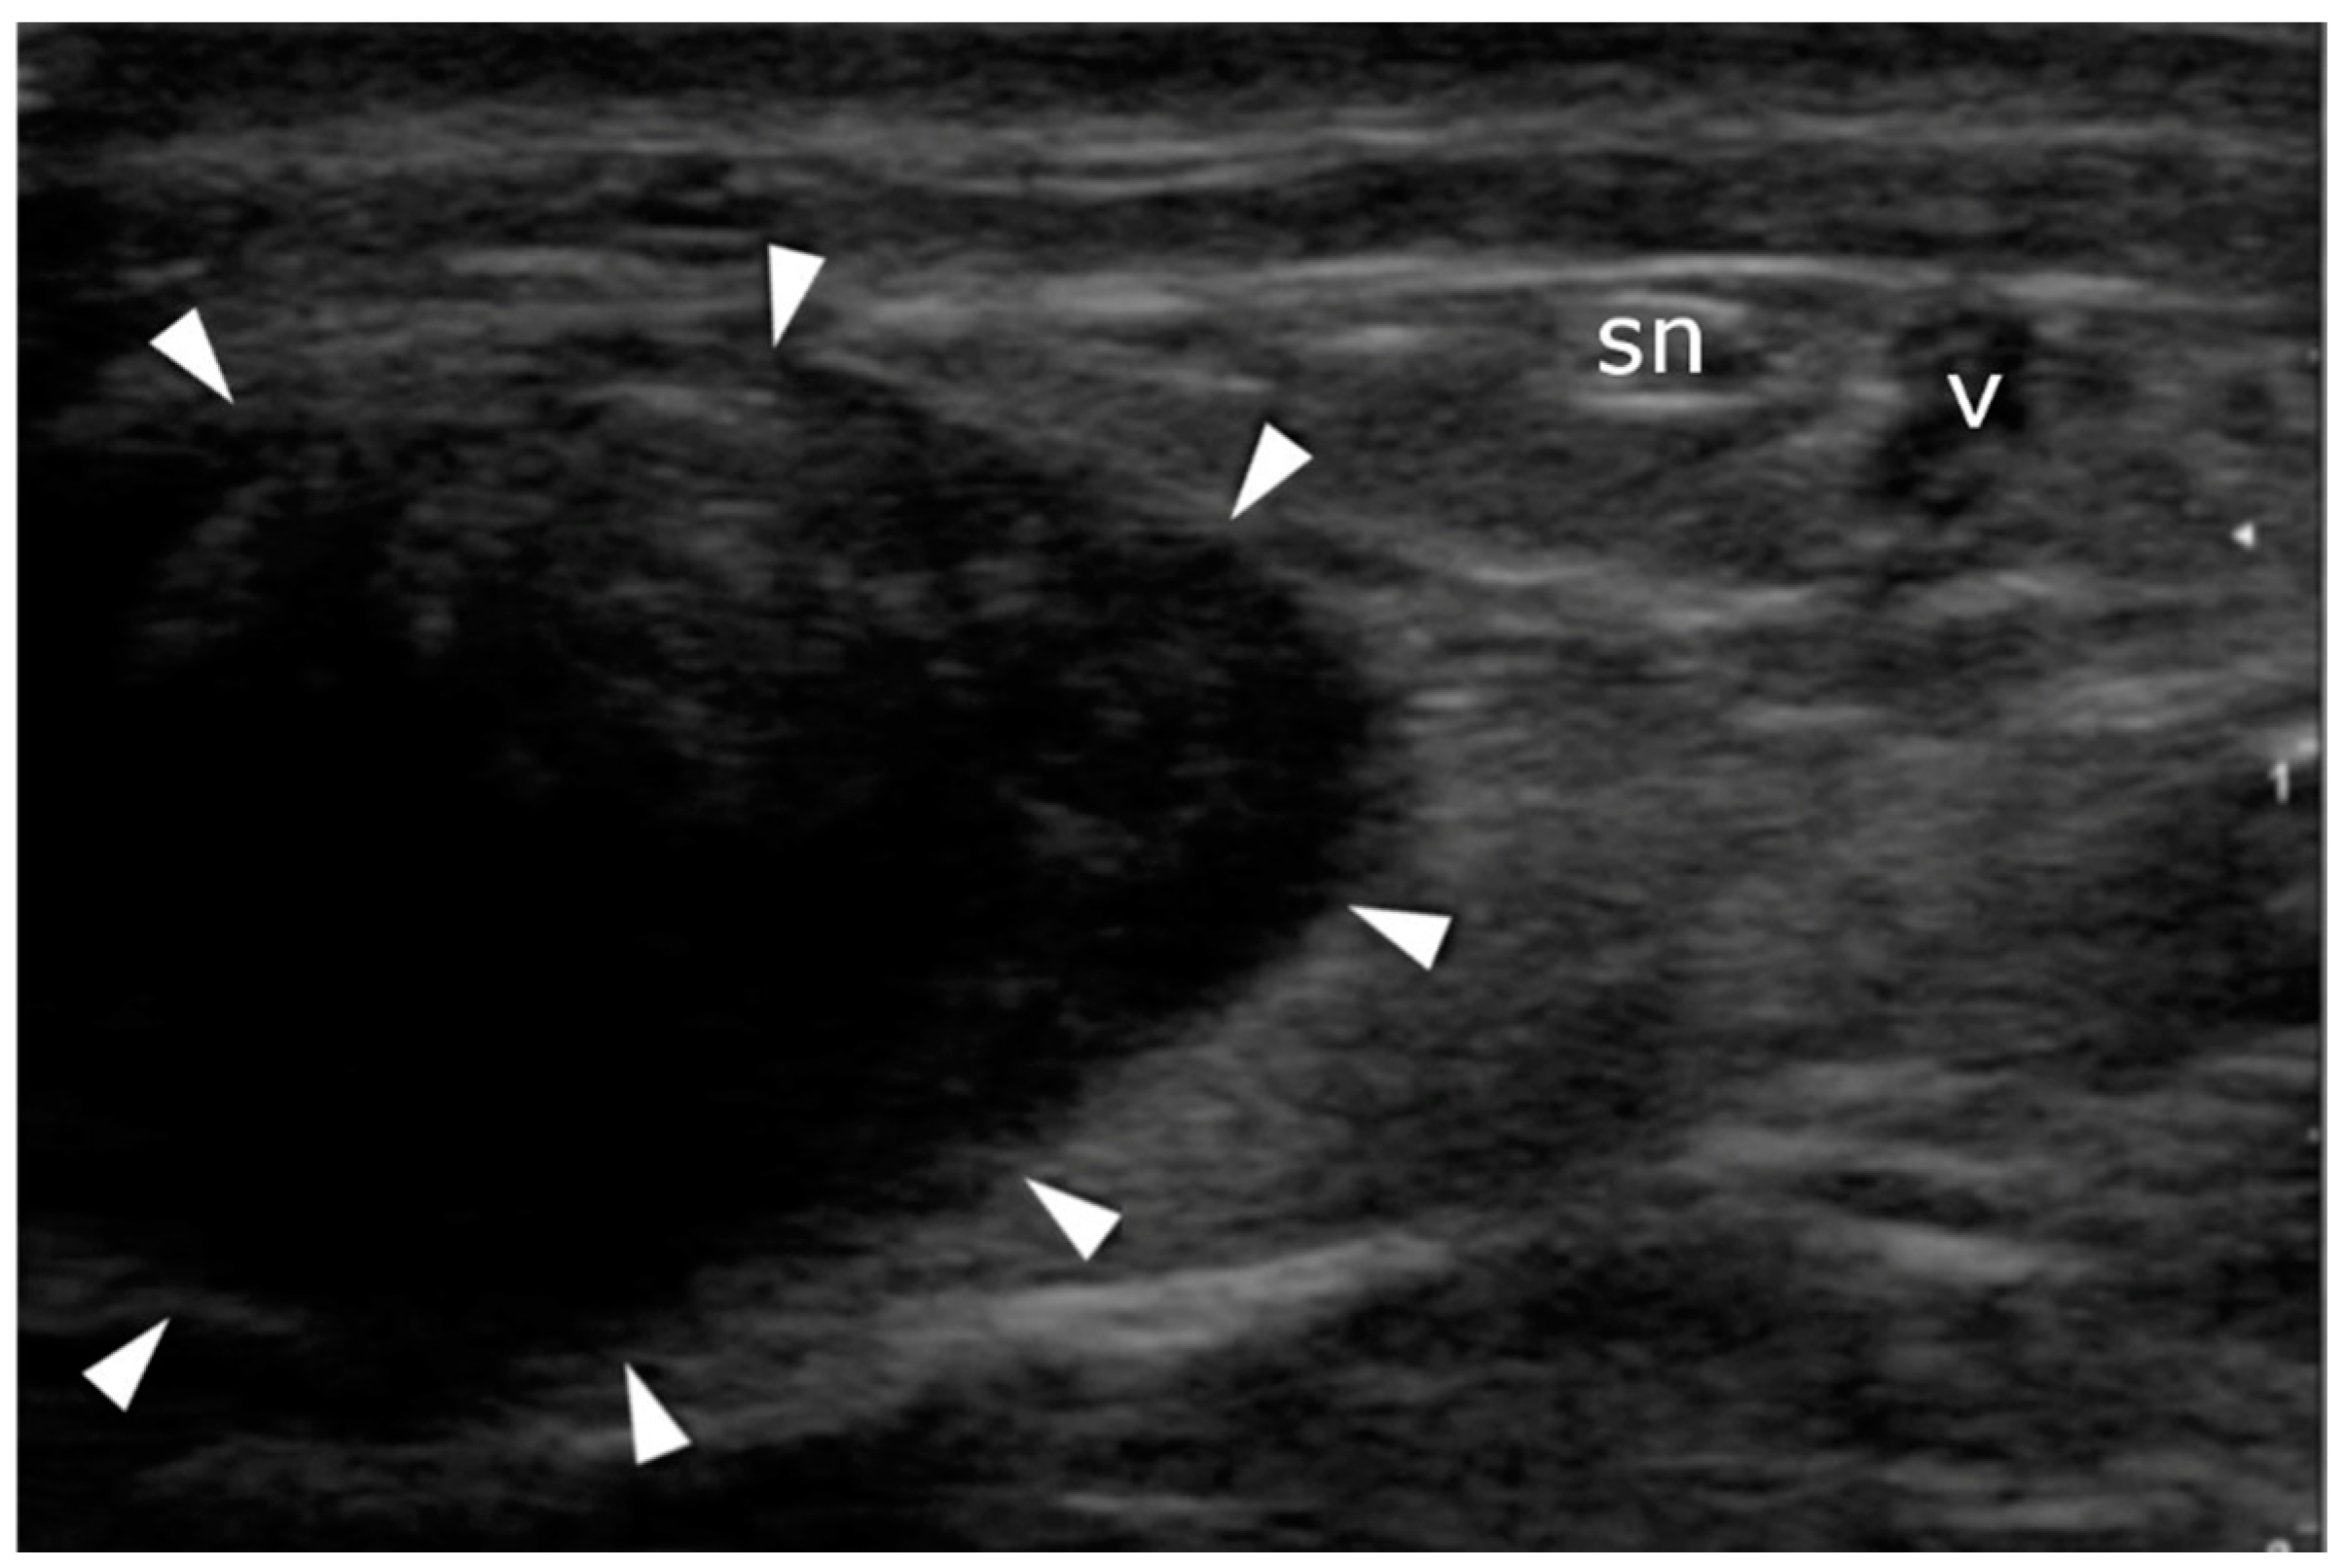

Six sutures (Number 1 Maxon), three of which were situated proximally and the other three distally (2, 4, and 6 cm) to the rupture side, were passed transversally through the tendon stumps. In the US-guided group, sonographic visualization was performed as discussed below to pass the needle through the center of the tendon and avoid the sural nerve (Figure 3, Figure 4 and Figure 5). In the non-guided group, the surgeons relied on characteristic anatomical spots and tissue palpation during suture deployment. In both groups, forceps were used to separate the AT from the subcutaneous tissue. The sutures were then passed back out to the area of the initial transverse incision. Plantar flexion of 20° was applied. The sutures were tied to allow stump approximation and buried in the subcutaneous layer of the tissue. The skin incisions were closed using non-absorbable sutures (Number 3.0 Dafilon) and sterile dressings were applied. The extremity was immobilized in a below-knee walker brace with heel support to maintain 20° plantar flexion.

Figure 5.

Sural nerve identification: transverse plane. The nerve (sn) and vein (v) pass on the lateral side of the Achilles tendon (arrowheads).

A high-resolution real-time ultrasound examination was performed in the operation room. We used a sterile draped high-frequency (10–12 MHz) linear probe. Transverse scans were used to localize the SN. It was followed from the proximal area of the calf—where it laterally follows the saphenous vein in its fascial compartment between the two heads of the gastrocnemius—to the distal area and the lateral malleolus area. The SN’s echogenicity is oval and typical of nerves, showing hyperechogenic spots in the hypoechogenic area surrounded by the hyperechogenic sheath (Figure 5, Supplementary Material Video S1). The entry point and the angle of the needle were chosen with direct US guidance (Figure 6, Supplementary Material Video S2). The suture course was checked before it entered the skin incision (Figure 7, Supplementary Material Video S3).